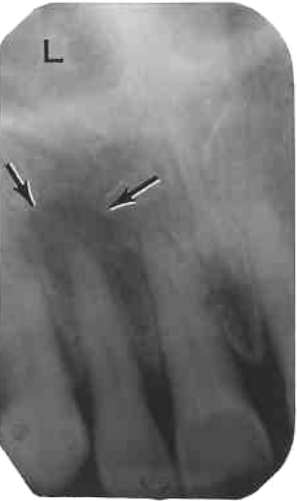

26. What is shown by L?

27. What is L showing?